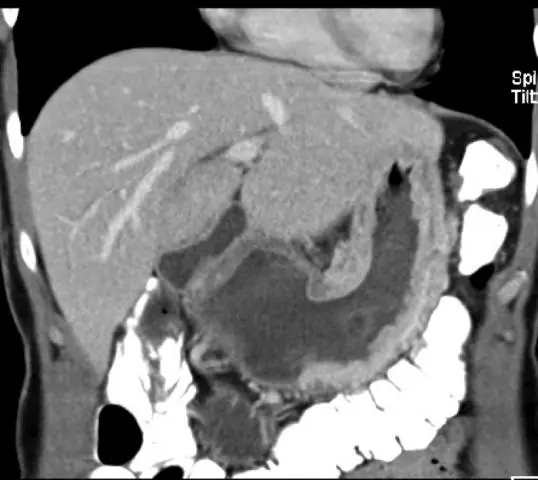

Независимые SL и ПК являются частью стандартного алгоритма постановки для любого пациента с клинической стадией поражения T2 или выше. Время от времени пациенты с повреждениями T1 будут подвергаться SL и PC, если есть признаки высокого риска, или во время лапаротомии и попытки резекции. SL и PC выполнялись до какого-либо окончательного лечения с использованием стандартной методики, используемой в нашем учреждении, как описано ранее (5, 6, 16, 17, 18, 19, 20). Брюшная полость была осмотрена на предмет грубых признаков метастазирования. Все макроскопические поражения брюшины были биопсии и отправлены на постоянное патологическое обследование. На рис. 1 приведен пример грубого перитонеального распространения при SL. Макроскопически положительная лапароскопия была определена как положительная биопсия визуализированного повреждения брюшины. После тщательного осмотра брюшной полости было выполнено цитологическое исследование брюшной полости. ПК считался положительным в любом случае «злокачественных клеток» или «аденокарциномы» при окрашивании гематоксилином и эозином (H & E), и / или «атипичных клетках» или «подозрительных на злокачественность» при окрашивании H & E с окрашиванием подтверждающей иммуногистохимией (IHC) (21, 22). Хотя имеется широкий спектр иммуноокрашиваний, включающих маркеры как эпителиальных, так и мезотелиальных клеток, МОС-31 надежно дифференцирует аденокарциному (23). Патологоанатомы в нашем учреждении использовали IHC в наших цитологических образцах с начала 1990-х годов, и наша практика была относительно стабильной в этот период (24, 25, 26, 27).

Грубый карциноматоз на стадии лапароскопии. Пациент с аденокарциномой срединного отдела желудка с серозной инвазией и карциноматозом брюшины. b Пациент с дистальной аденокарциномой желудка и грубым перитонеальным карциноматозом, выявленным на стадии лапароскопии